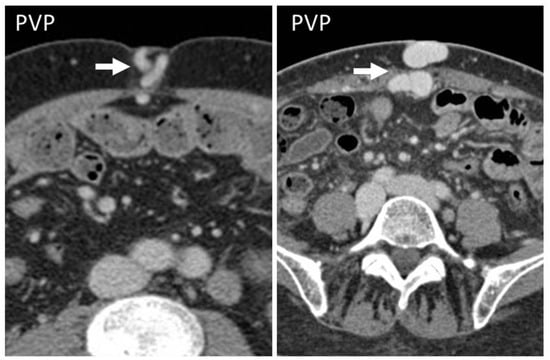

Figure 8. CT appearance of “caput medusae” on axial, contrast-enhanced CT scan on portal venous phase in two cirrhotic patients, as a result of the recanalization of the umbilical vein due to portal hypertension. This appearance is due to tortuous vessels (arrows) reaching the abdominal wall at the level of the navel.